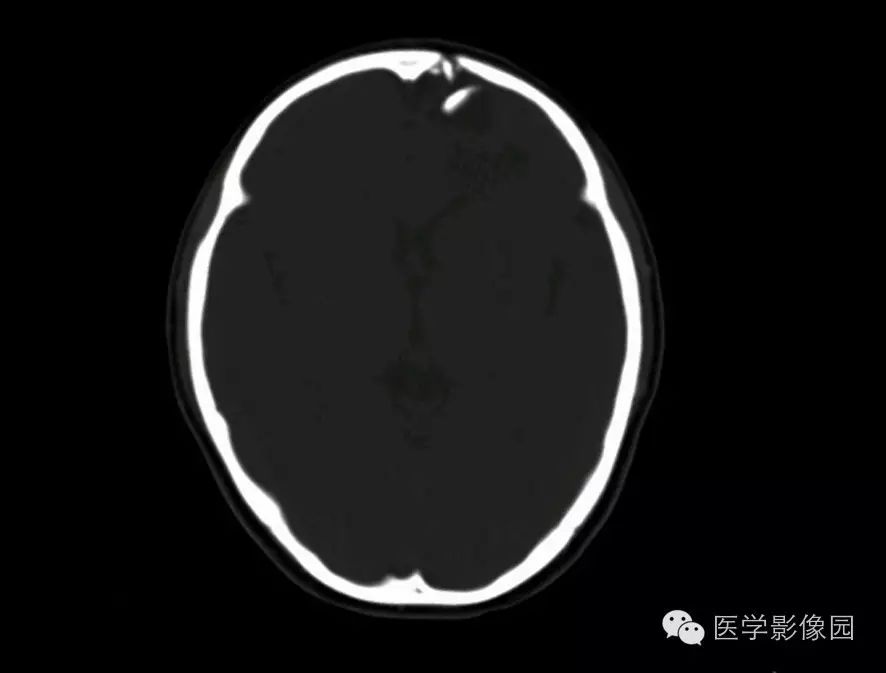

颅骨粉碎性骨折并上矢状窦损伤并硬膜外血肿并脑疝形成

颅底ct高清图解 常见骨折部位图示

2)外伤后鼻窦或者乳突气房内可见气液平面或充满液体,这也是颅底骨折